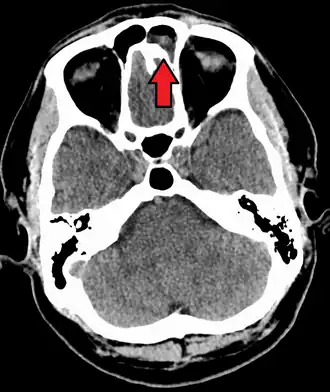

-

CT of chronic sinusitis -

CT scan of chronic sinusitis, showing a filled right maxillary sinus with sclerotic thickened bone -

MRI image showing sinusitis. Edema and mucosal thickening appear in both maxillary sinuses. -

Maxillary sinusitis caused by a dental infection associated with periorbital cellulitis -